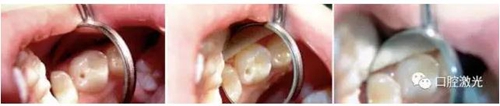

案例1:兒童口腔去齲

9歲男童上左側(cè)磨牙溝窩齲齒。整個治療過程無需麻醉。

案例2:成人口腔去齲

39歲男性患者,下右側(cè)牙頸部齲。治療過程無需麻醉